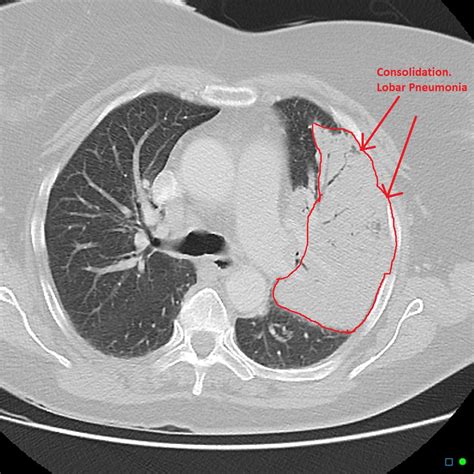

Once the scan is completed, a radiologist will interpret the images and generate a report. When viewing a Pneumonia CT Scan, medical professionals look for specific patterns of lung involvement. These patterns often indicate the type of pneumonia or the severity of the inflammatory response.

Common findings often described in reports include:

• Consolidation: This refers to the filling of air spaces (alveoli) with fluid, pus, or other material, appearing as dense, white areas on the scan.

• Bronchograms: The appearance of air-filled bronchi surrounded by consolidated lung tissue.

It is important to remember that these findings must always be correlated with the patient's symptoms, laboratory results, and clinical history. A report with "positive findings" does not always imply a worst-case scenario, as many patterns are typical of common bacterial or viral infections.